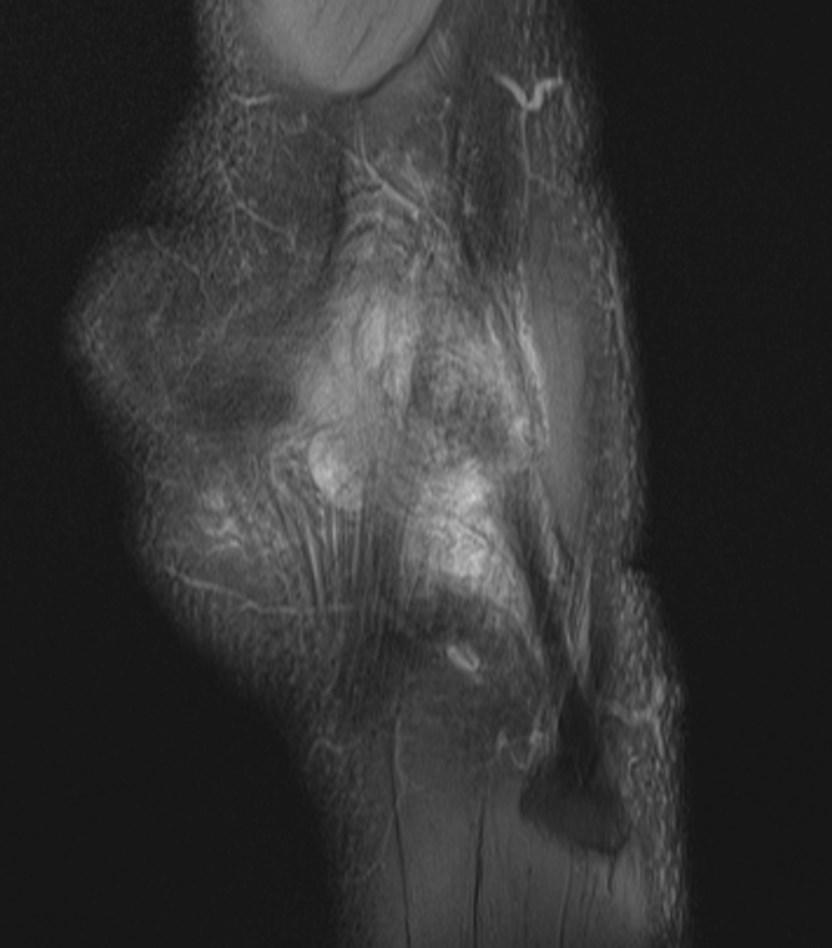

*49-year-old male present with pain above the lateral margin of the knee.

What is the most likely diagnosis?

Answer: Iliotibial band (friction) syndrome

MR images revealed high signal intensity in the fluid sensitive sequences involving the fat planes between the iliotibial band and lateral femoral condyle. There is no significant thickening of the iliotibial band or abnormal signal intensity.

Iliotibial band syndrome is a common cause of lateral knee pain related to intense physical activity resulting in chronic inflammation.

Differential diagnosis: lateral meniscal tear, lateral collateral ligament injury